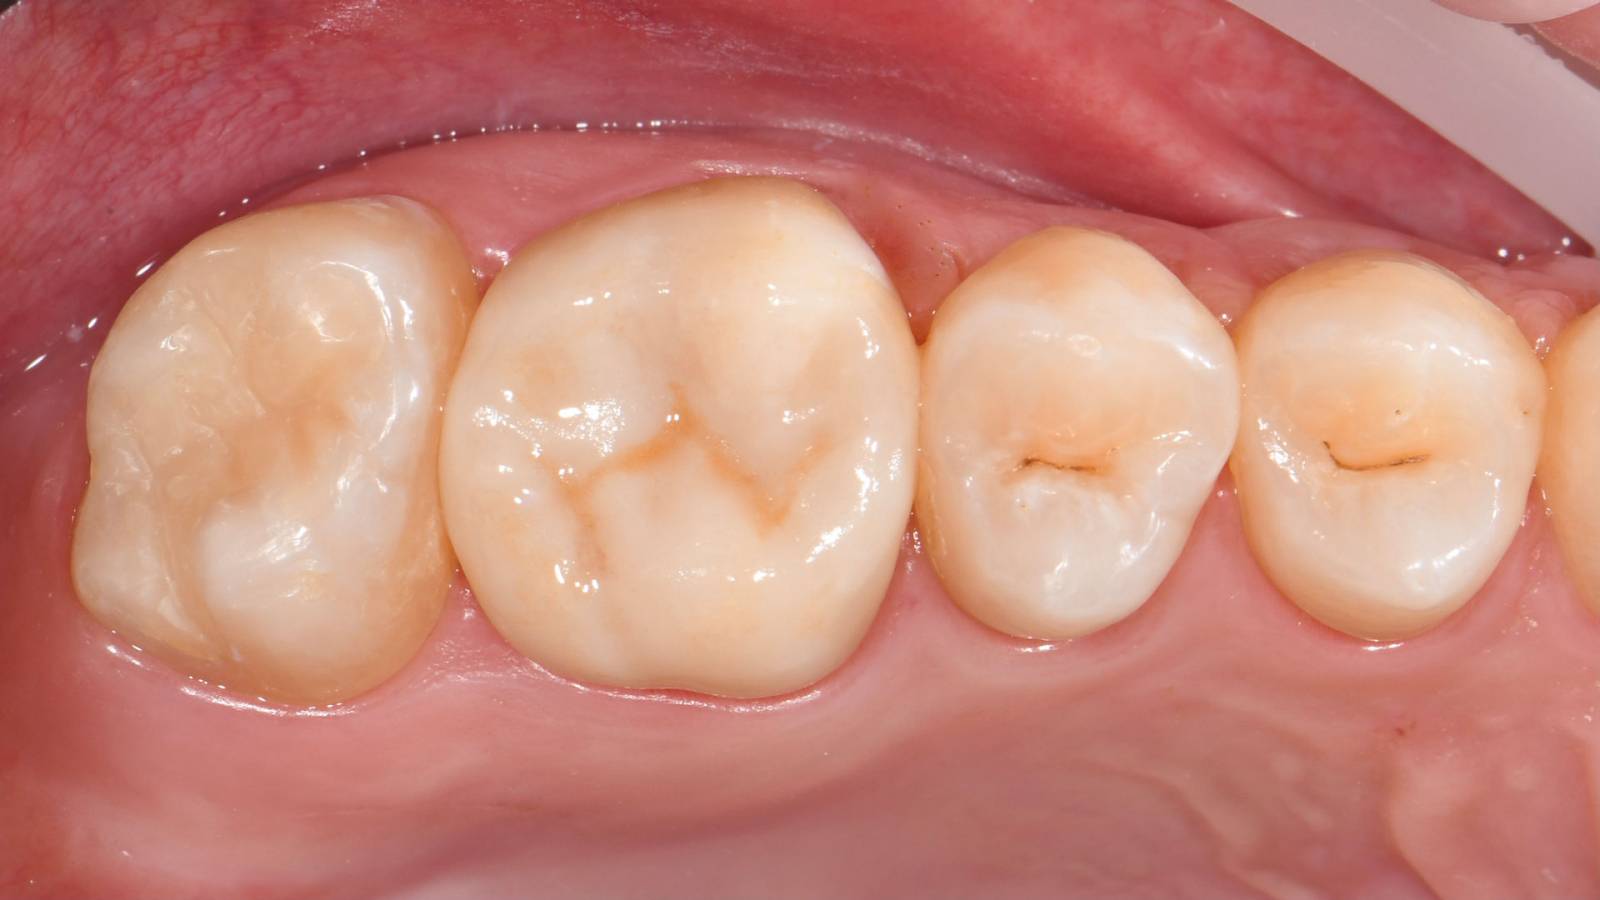

Before

Fractured ceramic restoration made from a leucite-reinforced glass-ceramic after a clinical service time of 12 years.